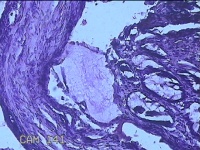

性别

男

年龄

40岁

临床诊断

混合痔

一般病史

反复肛门肿物突出15年。

标本名称

肛门肿物

大体所见

灰白暗红色肿物0.7x0.5x0.2cm一个,表面糜烂。

脱水、透明,浸蜡、脱蜡效果不佳,制片质量差。